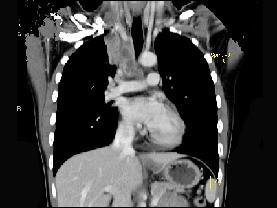

问题 男,21岁,干咳,盗汗一月伴消瘦,CT如图,应先考虑为 ( )

选项 A、右上肺上沟瘤 B、右上肺不张 C、纵隔型肺癌并纵隔淋巴结核转移 D、淋巴瘤 E、右上肺结核并纵隔淋巴结核

答案 E